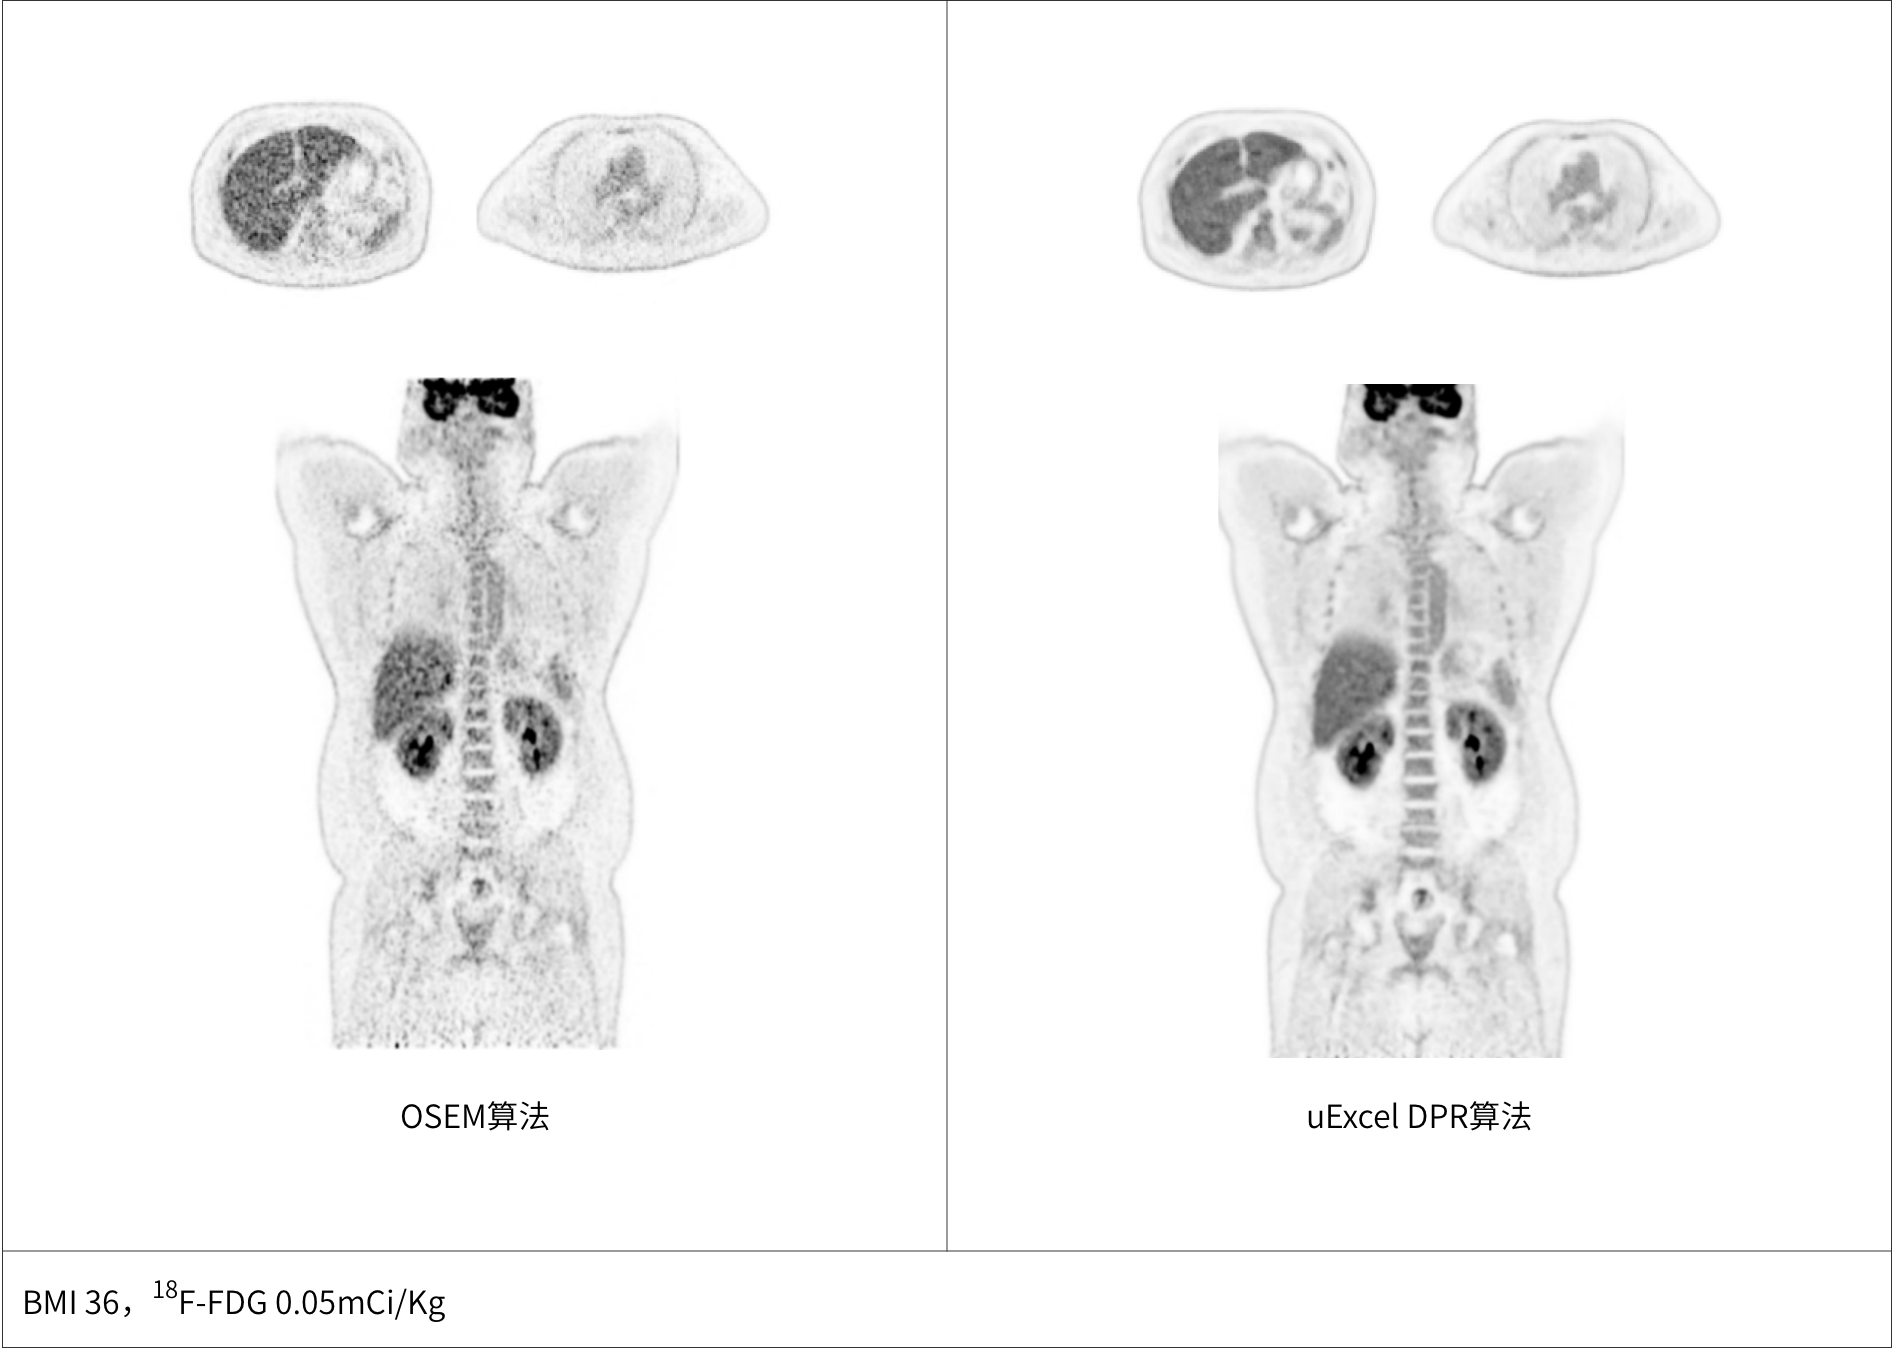

uExcel DPR*全面优化PET-CT扫描条件

同时实现图像对比度、噪声、信噪比三重优化

大体重患者主动脉血管结构清晰显示